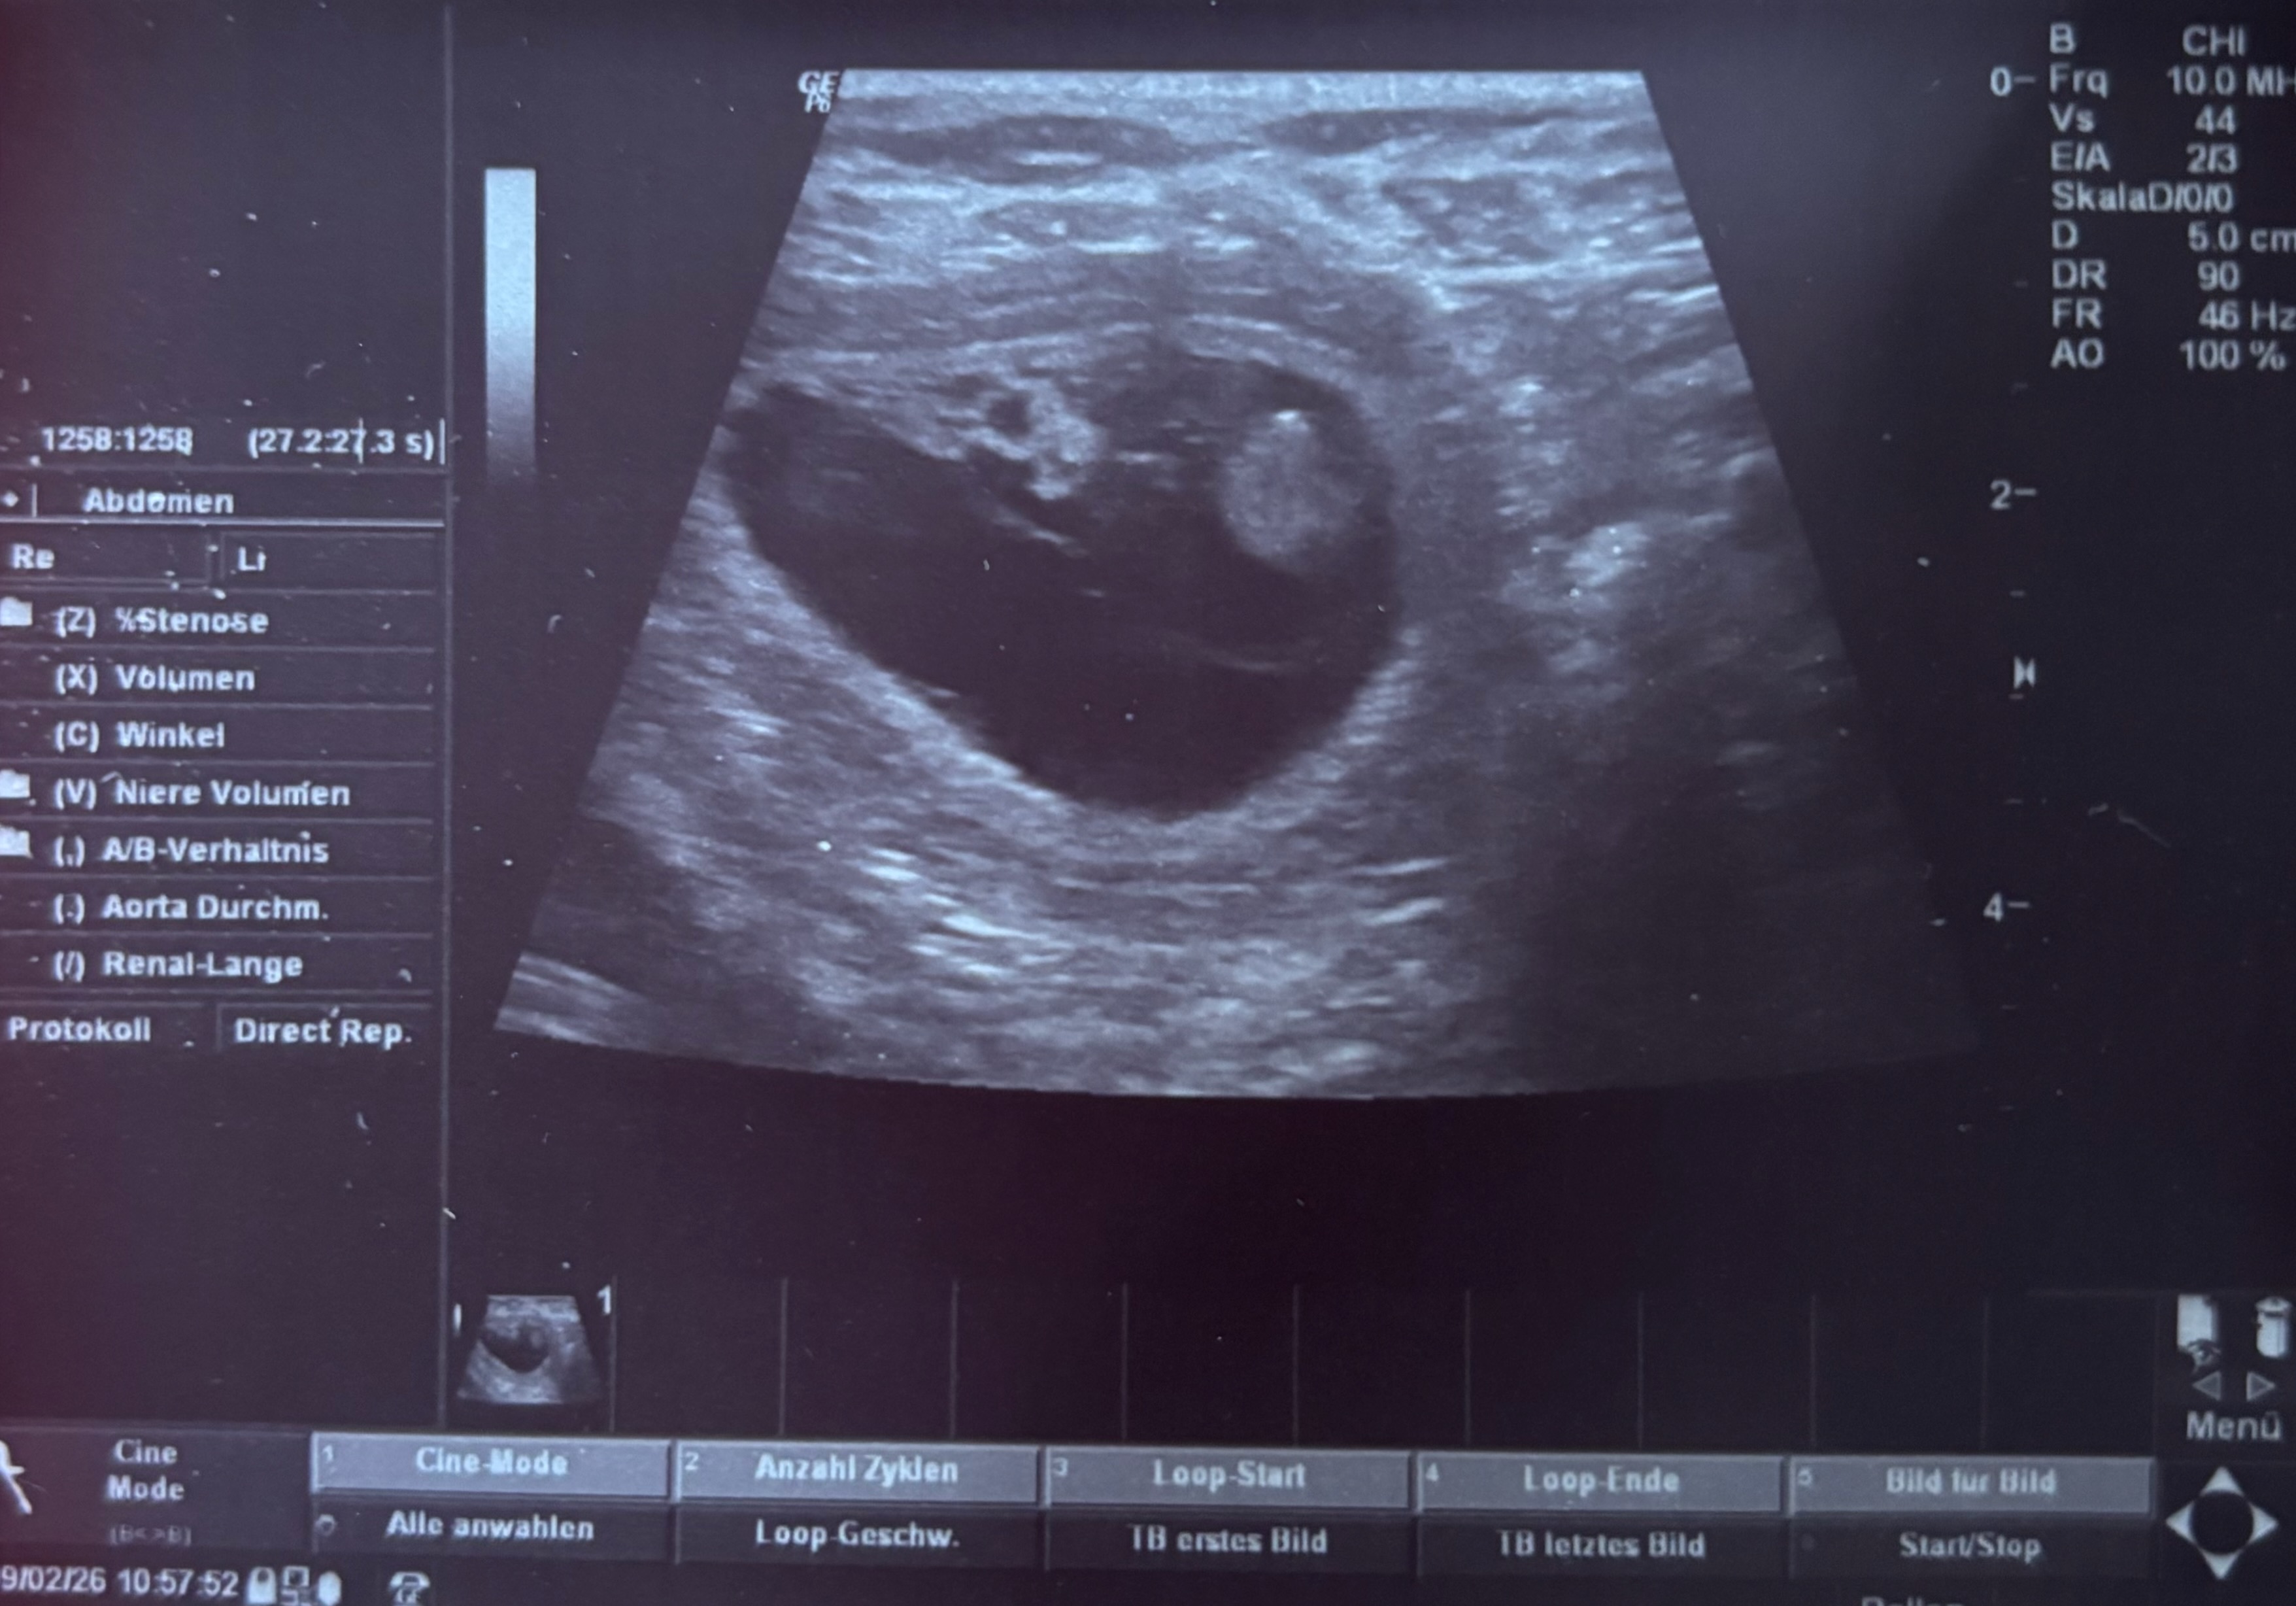

Mit großer Vorfreude können wir bekannt geben, dass unser G-Wurf auf den Weg gebracht wurde!

Wenn die Natur mitspielt, erwarten wir die Welpen der beiden Schönen um den 16. März 2026.